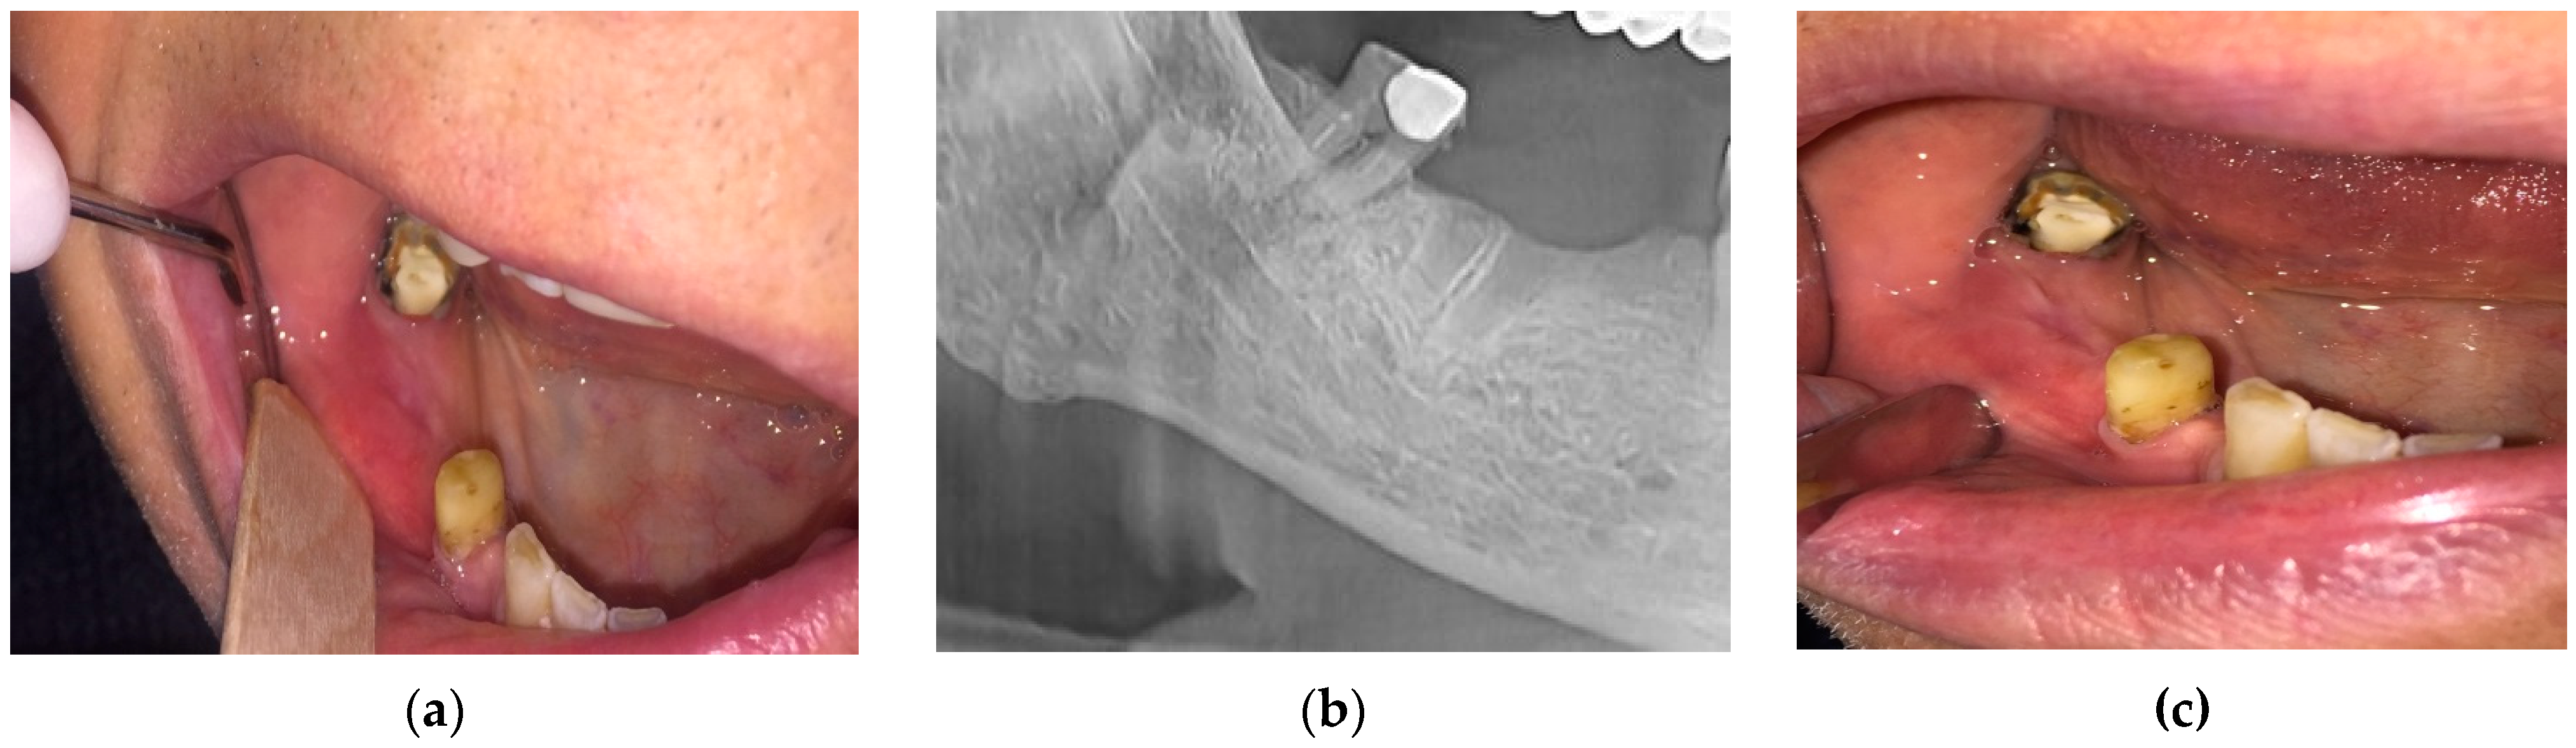

- For the n = 84 patients from the “at risk” group, the extractions were performed under the protocol mentioned above. The healing was complete with a spontaneous bone coverage in all cases. An example of the evolution of such a case is presented in Figure 1.

- (b)

- (c)